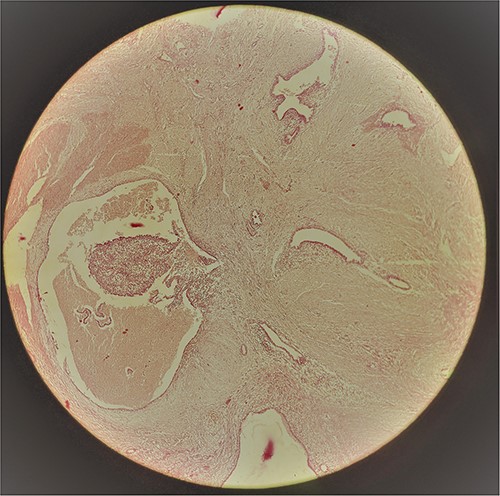

A 29-year-old female patient presented with a complaint of pain in lower abdomen for last 2 years. The pain would aggravate during menses. She also complained of a swelling at the site of her previous lower segment caesarean section (LSCS) scar for 1 year, which had gradually increased in size. She had underwent LSCS two and half years back. Nothing else was significant in history. Examination revealed a well circumscribed, firm mass at the surgical scar site, slightly to the right of the midline, ⁓6 cm × 5 cm in dimensions, fixed to underlying structures, especially on contraction of the rectus abdominis. Ultrasonography showed a heterogenous mass in the relation to the scar. Magnetic resonance imaging (MRI) revealed a well-defined heterogenous lesion extending into right rectus abdominus muscle, 4.2*3.1*2.2 cm in size with multiple thin septations within it, suggestive of scar endometriosis. Intraoperatively an irregular mass lesion was found in the subcutaneous scar tissue and was noted to be invading the rectus abdominis (Fig. 1). Enbloc excision of the endometrioma along with the involved portion of rectus sheath and rectus abdominis muscle was done (Figs 2 and 3). In view of potential tension on the fascial closure onlay mesh reinforcement was also done. The post operative course was uneventful and the patient was discharged on 7th post operative day. The histopathological examination confirmed the presence of endometrial tissue within the excised mass with skeletal muscle bundles infiltrated by endometrial glands (Fig. 3). Patient is on regular follow up and is recurrence free at 9 months.

AWE is uncommon. Though it can occur spontaneously but is usually seen following gynaecological and obstetric procedures, like caesarean section [2]. And as expected the most common type of AWE is CSE. The incidence rates reported in literature vary widely, usually ˂1% [2], as most of the data is derived from case reports or series. The condition frequently follows caesarean section. The pathogenesis of CSE appears to be complex; however, the most widely accepted theory is the Implantation Theory, suggesting that endometriosis results from direct inoculation of endometrial cells into the wound during the surgical procedure followed by oestrogen driven growth [3]. Some reports have speculated a higher risk of endometriosis with Pfannenstiel incision than a midline vertical incision, however the evidence is insufficient [4]. Presentation may vary with pain and/or mass being the most common features reported in up to 80% cases [5]. The triad of a palpable tumour, cyclic pain and a history of caesarean section, called the Esquivel triad is almost diagnostic of AWE [6]. A cyclical pattern of pain with worsening during menstruation provides a valuable clue to diagnosis. The time interval between the index surgery and the manifestation varies and in this patient was 6 months. Ultrasonography is the initial imaging modality employed. The characteristic appearance on ultrasonography is of a hyperechoic solid lesion with internal vascularity. Cross sectional imaging may be diagnostic, with MRI better than computed tomography in terms of resolution and soft tissue delineation [7]. Fine needle aspiration cytology (FNAC) is difficult to interpret in scar endometriosis and involves the possibility of needle track implantation [8]. Histopathology provides the definitive diagnosis and presence of endometrial glands, stroma or hemosiderin containing macrophages is diagnostic. Hernia, haematoma, lipoma, desmoids, metastatic tumours are the usual differentials. The management is primarily surgical but medical treatment with progesterone, antioestrogens such as danazol, and gonadotropic agonists like leuprolide acetate has been tried with poor success [9]. Excision with wide margins is critical to prevent recurrence. Invasion into muscles or aponeurosis warrants enbloc excision and a residual defect may need reinforcement with prosthetic mesh as was needed in this patient. Several protective measures like vigorous flushing of the wound cavity, obliteration of dead space have been suggested as strategies to decrease the incidence of CSE.